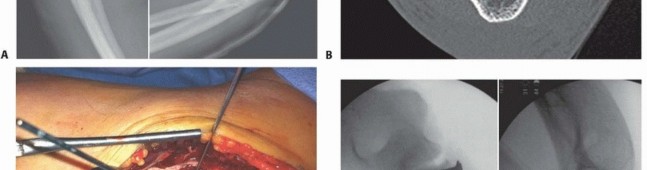

Meticulous preoperative planning is the cornerstone of a successful surgical outcome in elbow fracture-dislocations. High-quality plain radiographs in the anteroposterior (AP) and lateral planes must be obtained before and after any closed reduction attempts. However, cast material and overlapping osseous structures often obscure critical bony detail. Therefore, computed tomography (CT) scanning with thin cuts, multiplanar reformatted images, and three-dimensional (3-D) reconstructions is considered the gold standard and is mandatory for surgical planning. 3-D CT allows the surgeon to precisely understand the size, comminution, and spatial orientation of the coronoid and radial head fragments, dictating whether primary osteosynthesis is feasible or if arthroplasty will be required.

Step 2: Fix or Replace the Radial Head. Once the anterior buttress is restored, attention turns to the radial column. If the radial head fracture consists of two or three large, non-comminuted fragments, osteosynthesis is performed using countersunk headless compression screws or a low-profile "safe zone" plate. If the fracture is highly comminuted, radial head arthroplasty is mandatory. The radial head implant must be carefully sized; "overstuffing" the radiocapitellar joint will lead to capitellar wear, lateral elbow pain, and a failure to regain terminal flexion and extension. The implant should track smoothly against the capitellum and sit flush with or slightly proximal to the lateral edge of the intact coronoid.

Step 4: Assess Intraoperative Stability. Following LCL repair, the elbow is taken through a gentle range of motion. The surgeon must assess stability within a functional arc of 30 to 130 degrees of flexion-extension with the forearm in full pronation. If the joint remains concentrically reduced without subluxation or gapping on fluoroscopy, the procedure is concluded.